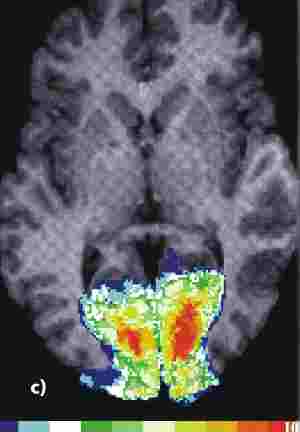

Die Änderung des NMR-Signals zB bei Verarbeitung eines visuellen Reizes sind sehr klein, und es ist oft nötig, mehrere Stimulationen durchzuführen und die dabei gemessenen Signale zu mitteln, um eine statistisch eindeutige (signifikante) Abweichung vom Ruhewert nachzuweisen. Das Ergebnis dieser statistischen Analyse wird dann in Form einer Falschfarbendarstellung einem Kernspintomogramm überlagert. Je wärmer der Farbton, desto stärker die gemessene Abweichung vom Ruhewert des NMR-Signals.

Quelle: "Forschen in Jülich" (1/2000)

Forschungszentrum Jülich

fmnrl.jpg